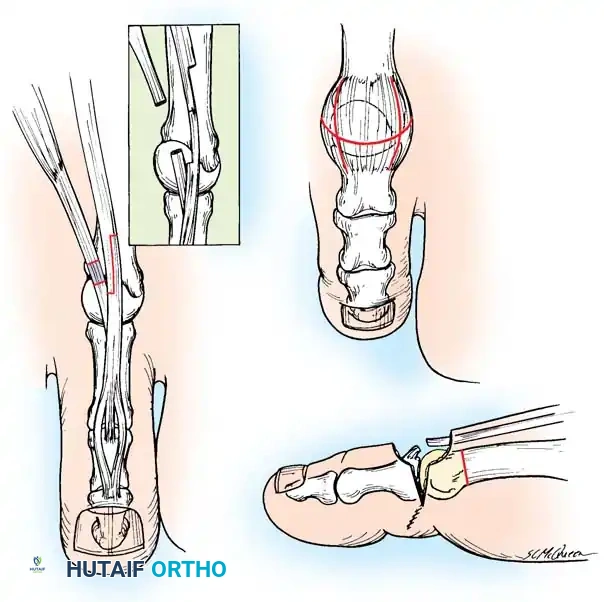

2. Jones Procedure (EHL to First Metatarsal Neck)

* Rationale: Corrects flexible clawing of the hallux and elevates the first ray.

* Technique: Transect the EHL at the IP joint. Reroute it through a drill hole in the neck of the first metatarsal and suture it back onto itself. The IP joint of the hallux must be arthrodesed to prevent a secondary drop-toe deformity.

Fig. 9: Biomechanical routing for tendon transfers in the correction of claw toe and forefoot equinus.